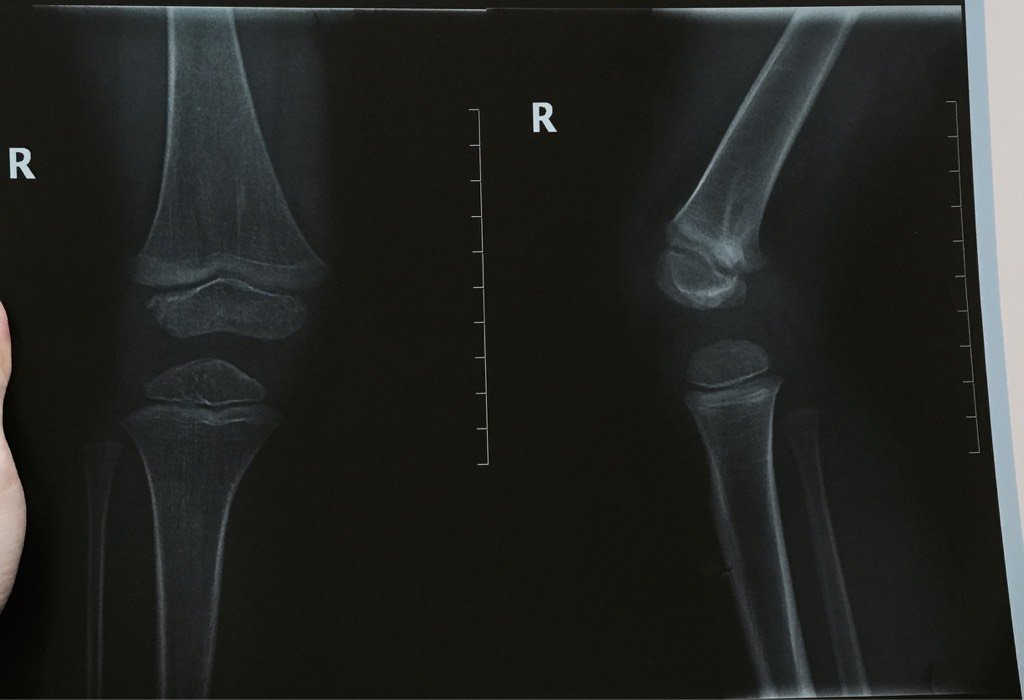

三岁宝宝从不高处跳下,右脚关节疼痛,去医院拍片说是股骨远股骨折,绑了固定支架5天了,支架很笨重,宝

三岁宝宝从不高处跳下,右脚关节疼痛,去医院拍片说是股骨远股骨折,绑了固定支架5天了,支架很笨重,宝宝又摔了一下,严重吗?很担心。请问这个骨折是不是就是骨骺损伤了?